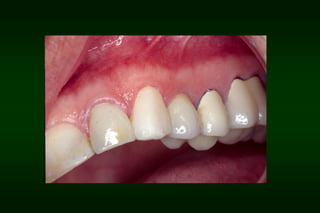

Requirements of Provisional Restoration III.Esthetic requirement: – – Resemble natural teeth Color stability

Types of Provisional Restoration II.Customized resin restorations 3. Indirect-direct (combination) technique 1. 2. 3. 4. 5. 6. 7. Advantages: Allows trial of esthetics, function and speech Provides template for the definitive restoration Ensures color stability Allows incorporation of reinforcement Saves chair time Permits removal and immediate replacement of nonsalvageable teeth Permits long-term treatment